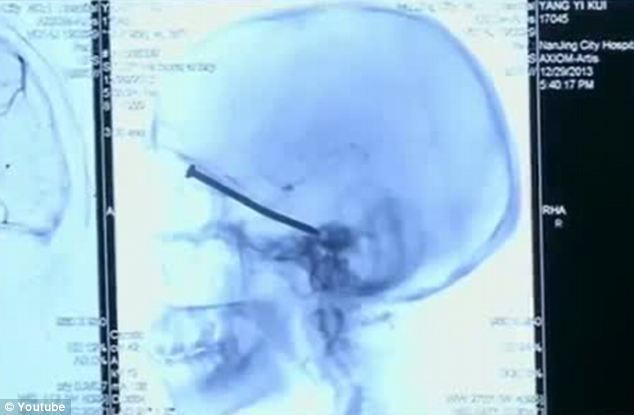

一名中國男子在幾天前裝修自己的房間時忽然感到眼周輕微刺痛,但是直到幾日后去醫(yī)院檢查時才發(fā)現(xiàn)原來一枚約8厘米長的釘子被射入了自己的頭部。